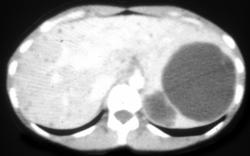

Splenic Hemangioma in Patient Klippel-Trenaunay-Weber (KTW) Syndrome